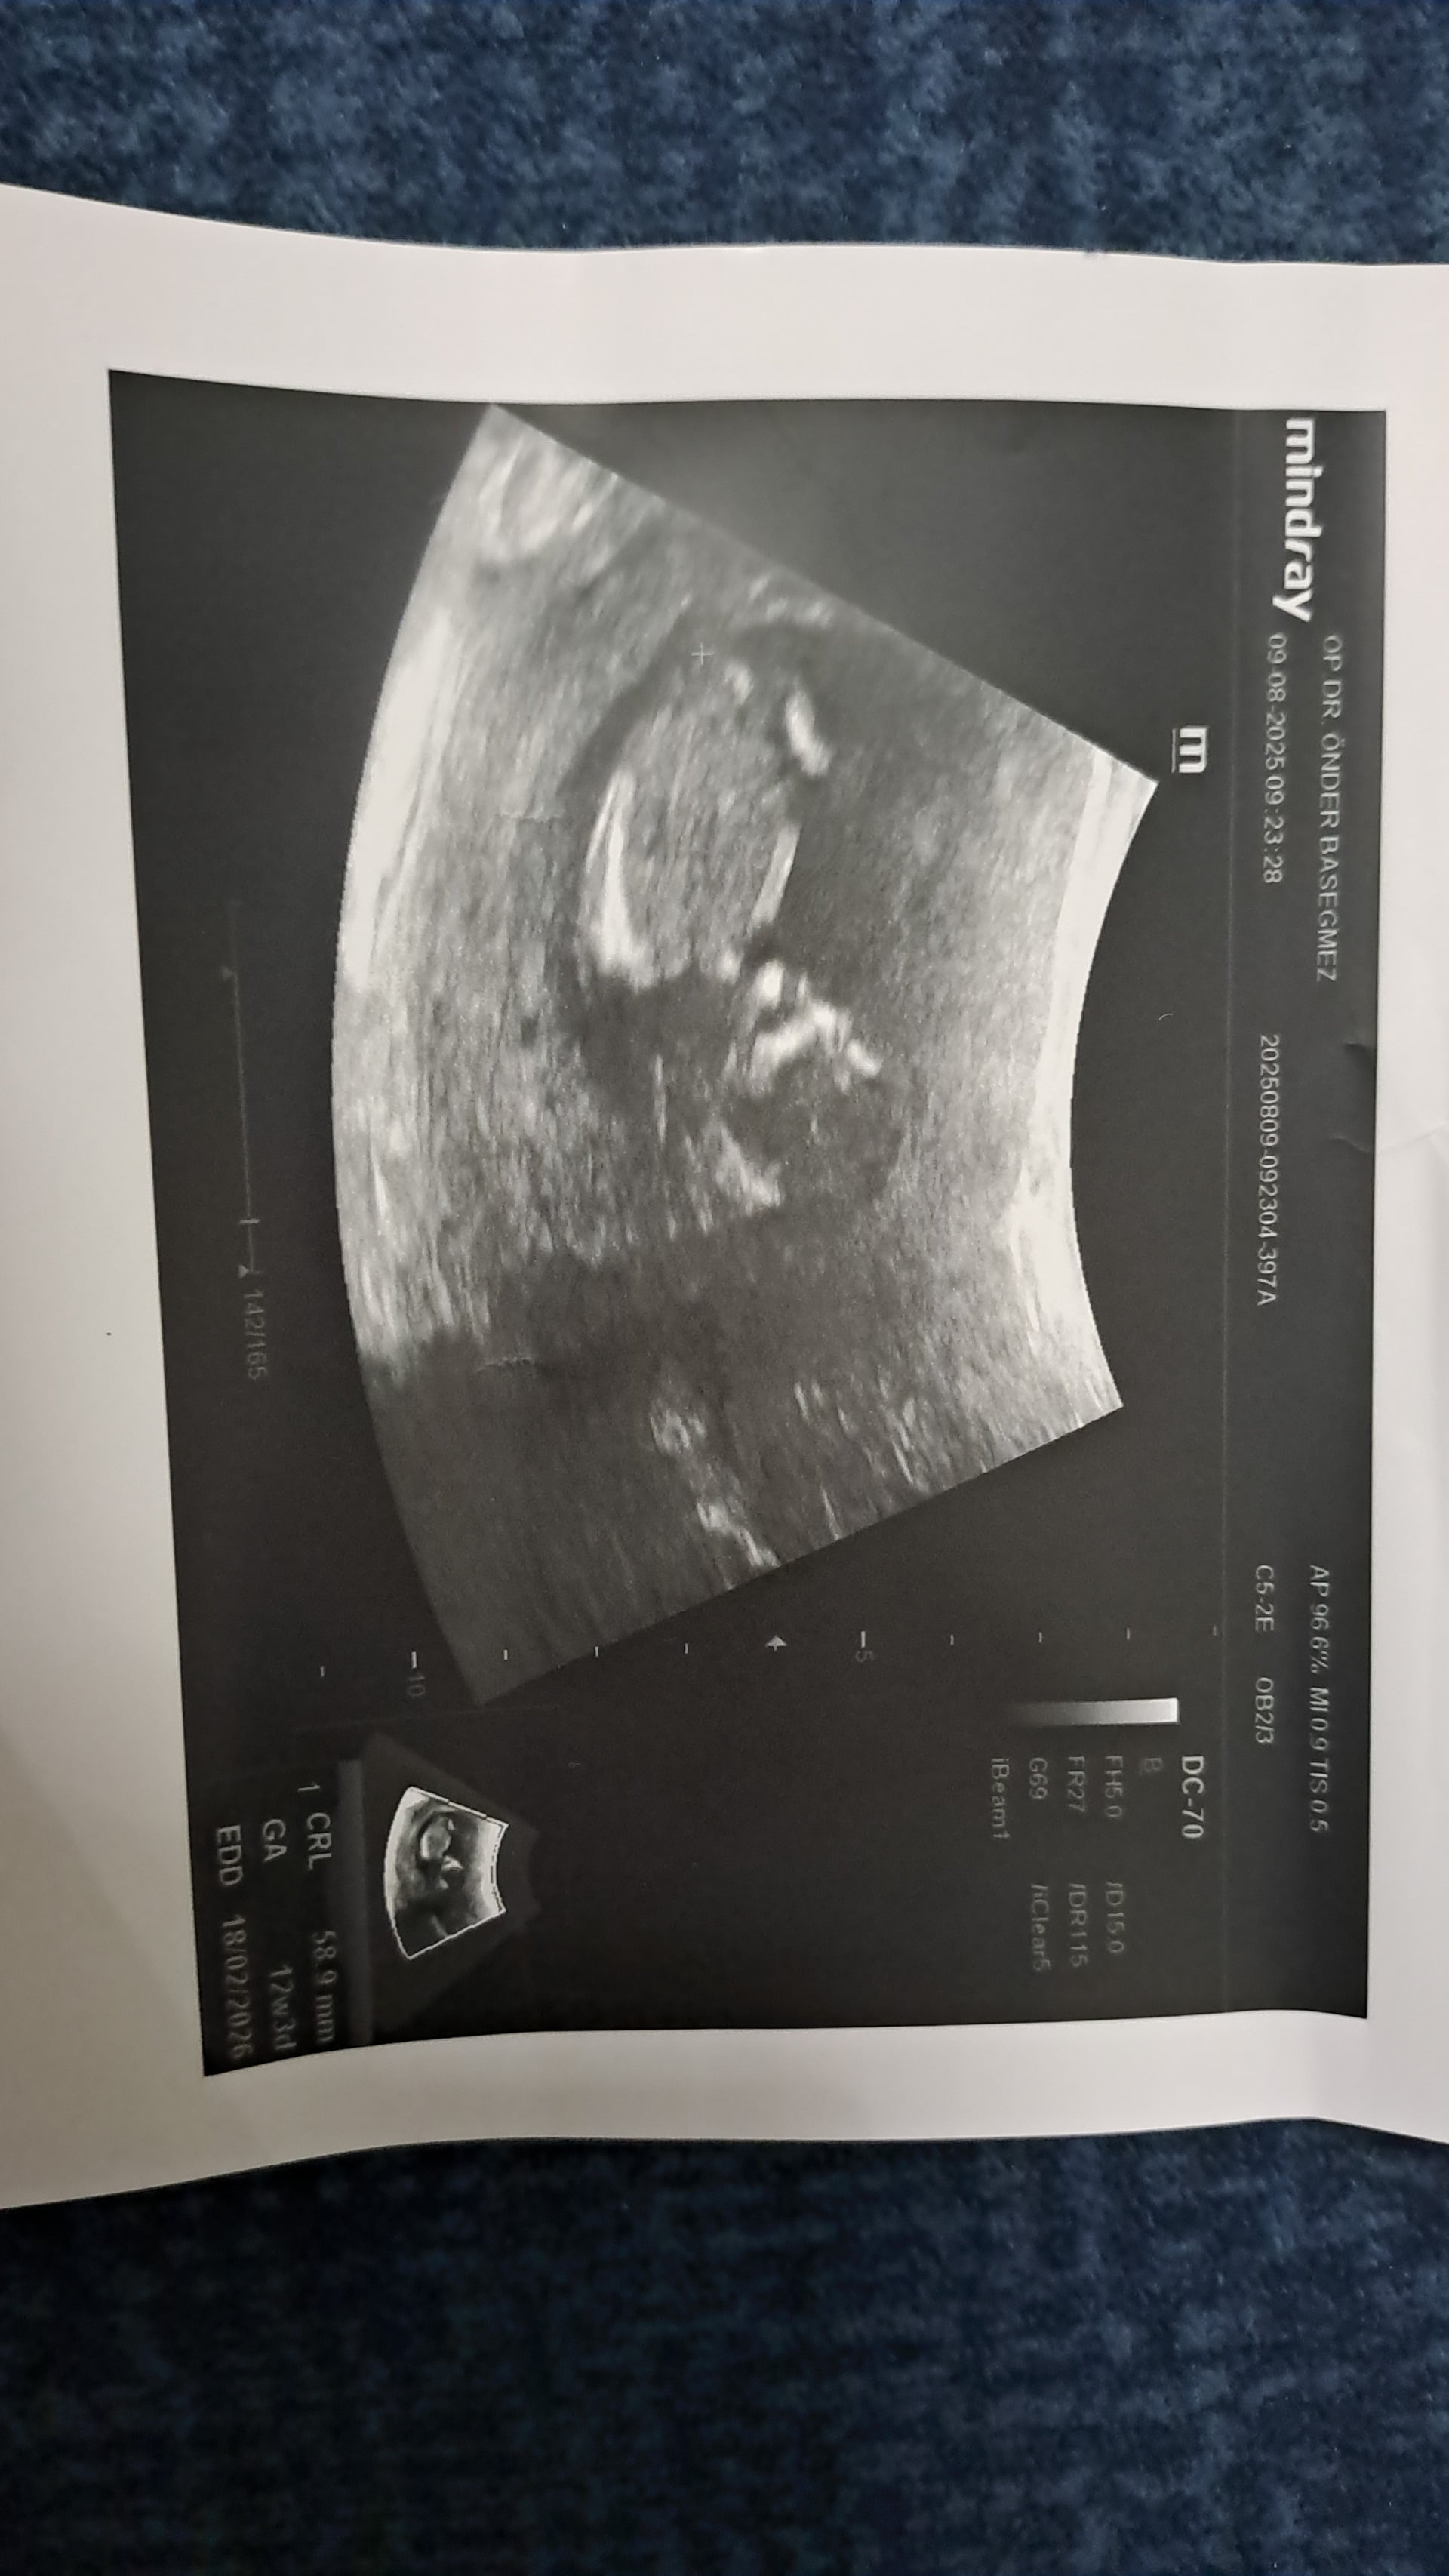

Erkek bebiş kesesi gibi ![]()

@Neriman Kız bebek kesesi canım biraz daha büyüyünce tekrar atarsın bakarız ama prenses gibi geldi bana

Burda kese yuvarlak benim kesemede benzettim erkek gibi duruyor büyümüş bebiş biz tahmin ediyoruz takdir Allah’ın daha belli olmadı mı önce ki kese şekline göre kız demiştim ama büyüyünce benim kesem gibi yuvarlak olmuş ve aşağıda tutunmuş hakkında hayırlısı olsun canım @Neriman Net öğrendiğim zaman etiketlersin beni